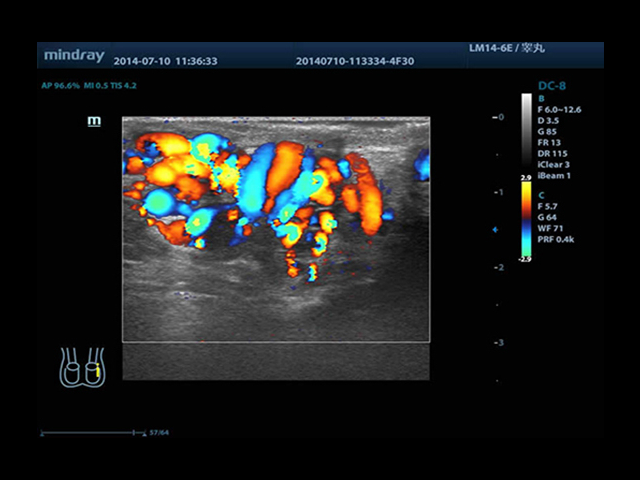

Mindray DC-8 Exp оснащен новым поколением датчиков с увеличенным количеством элементов и инновационной технологией "3T". Это позволяет достичь высокой детализации и качества изображения. Благодаря новейшей технологии iFlow, можно визуализировать даже самые мелкие сосуды и кровеносные пути.

• Высокочастотный линейный датчик 38 мм Mindray l14-6NE